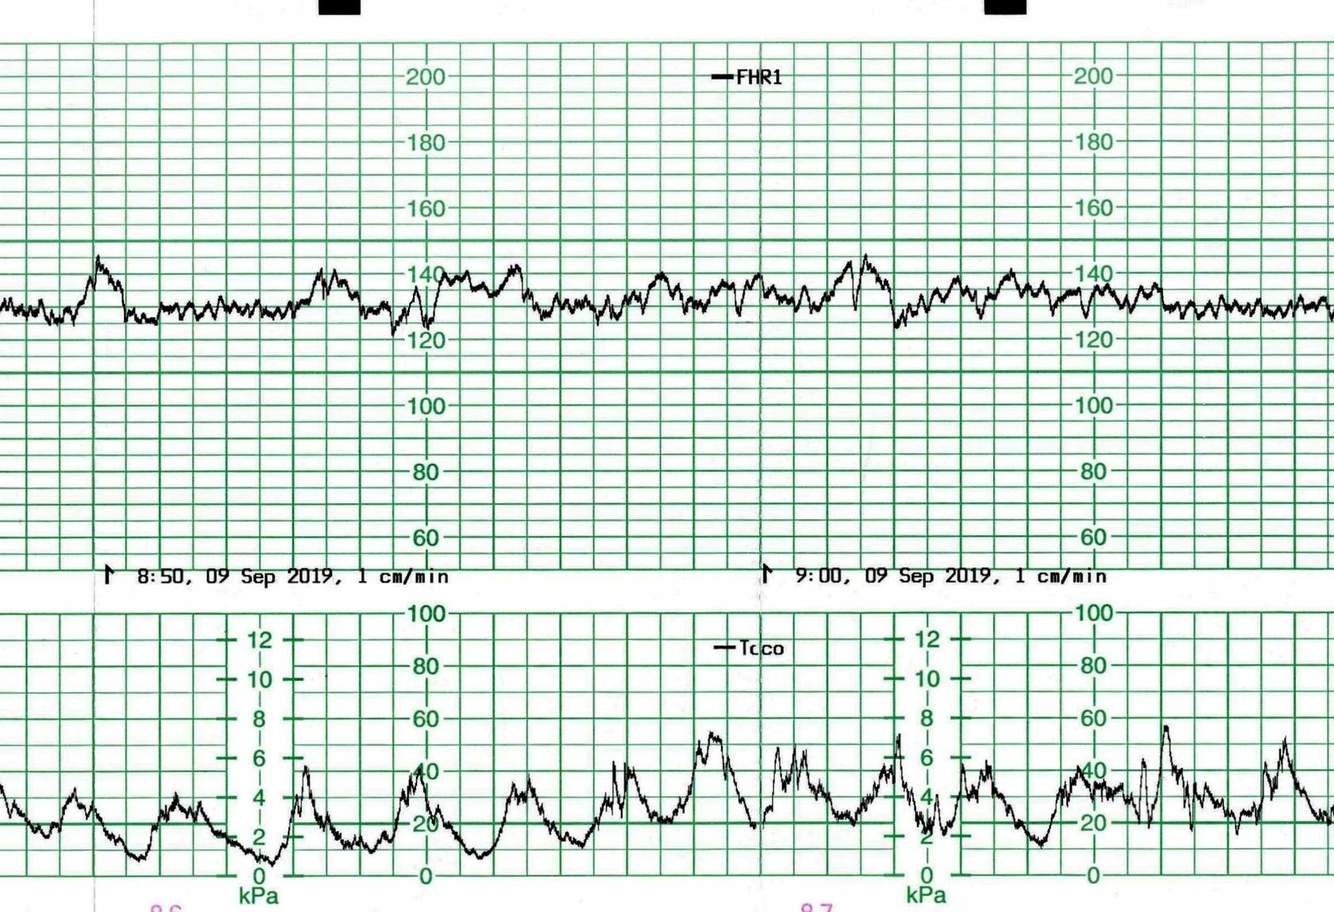

What uterine activity does this CTG represent?

Uterine hypertonus. Each contraction is lasting 2-3 minutes. The fetus is doing well at that point but is at risk.